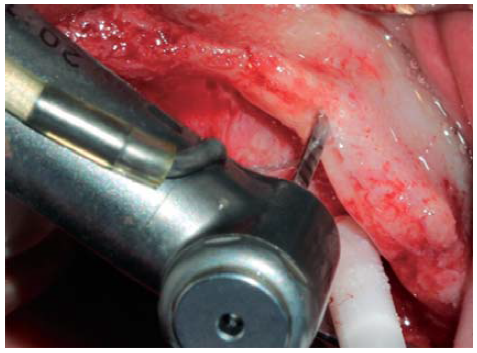

A full thickness incision over the crest was performed, raising a mucoperiosteal flap exposing bone table up to 4 mm from the top of the crest in vestibular direction; from that point the flap was divided into partial thickness (Figure 3). After this, impact points were marked in designated places according to surgical guide for implant placement; perforations were initiated with a 1.6 mm diameter burr in order to determine desired implant depth and axis. After this, a ridge was created on the crest with a diamond burr, fracturing cortical bone to create chisel's access to cancellous bone, and with the aforementioned, bone tables were separated until reaching a 5 mm depth (Figures 4 y 5). Perforations were further continued with a 2.0 diameter burr (Figure 6), and vestibular table expansion was undertaken creating greenstick fracture with the expanders, until reaching sufficient osseous bed diameter (3.2 mm diameter) (Figures 7 y 8). Implants were then placed at a 25 rpm speed and 35 Nem torque (Figures 9 y 10). After this, a particulate bovine bone graft was placed (Bonefill® Bionnovation Biomedical, Sao Paulo, Brazil) with the aim of preserving integrity of vestibular bone tables (Figure 11). All these procedures were repeated for placement of all six implants. Finally, sutures were undertaken with monofilament nylon 5/0.

Figure 4 Diamond disc (0.5 mm thick) used to create a crest groove passing through cortical bone and allowing access for bone chisel.